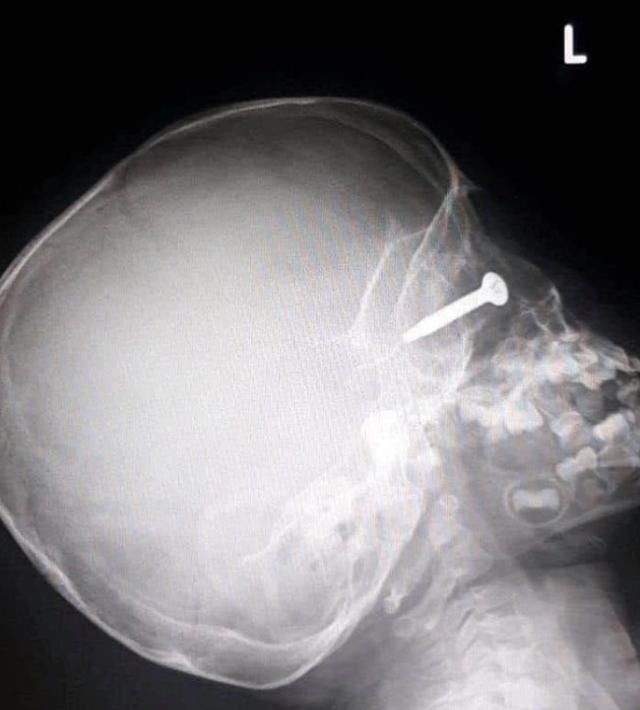

医生拍下了男孩受伤严重的照片,显示螺丝几乎完全深入男孩的眼球。

x光片还显示了螺丝在他眼窝里的深度——几乎达到他的头骨。